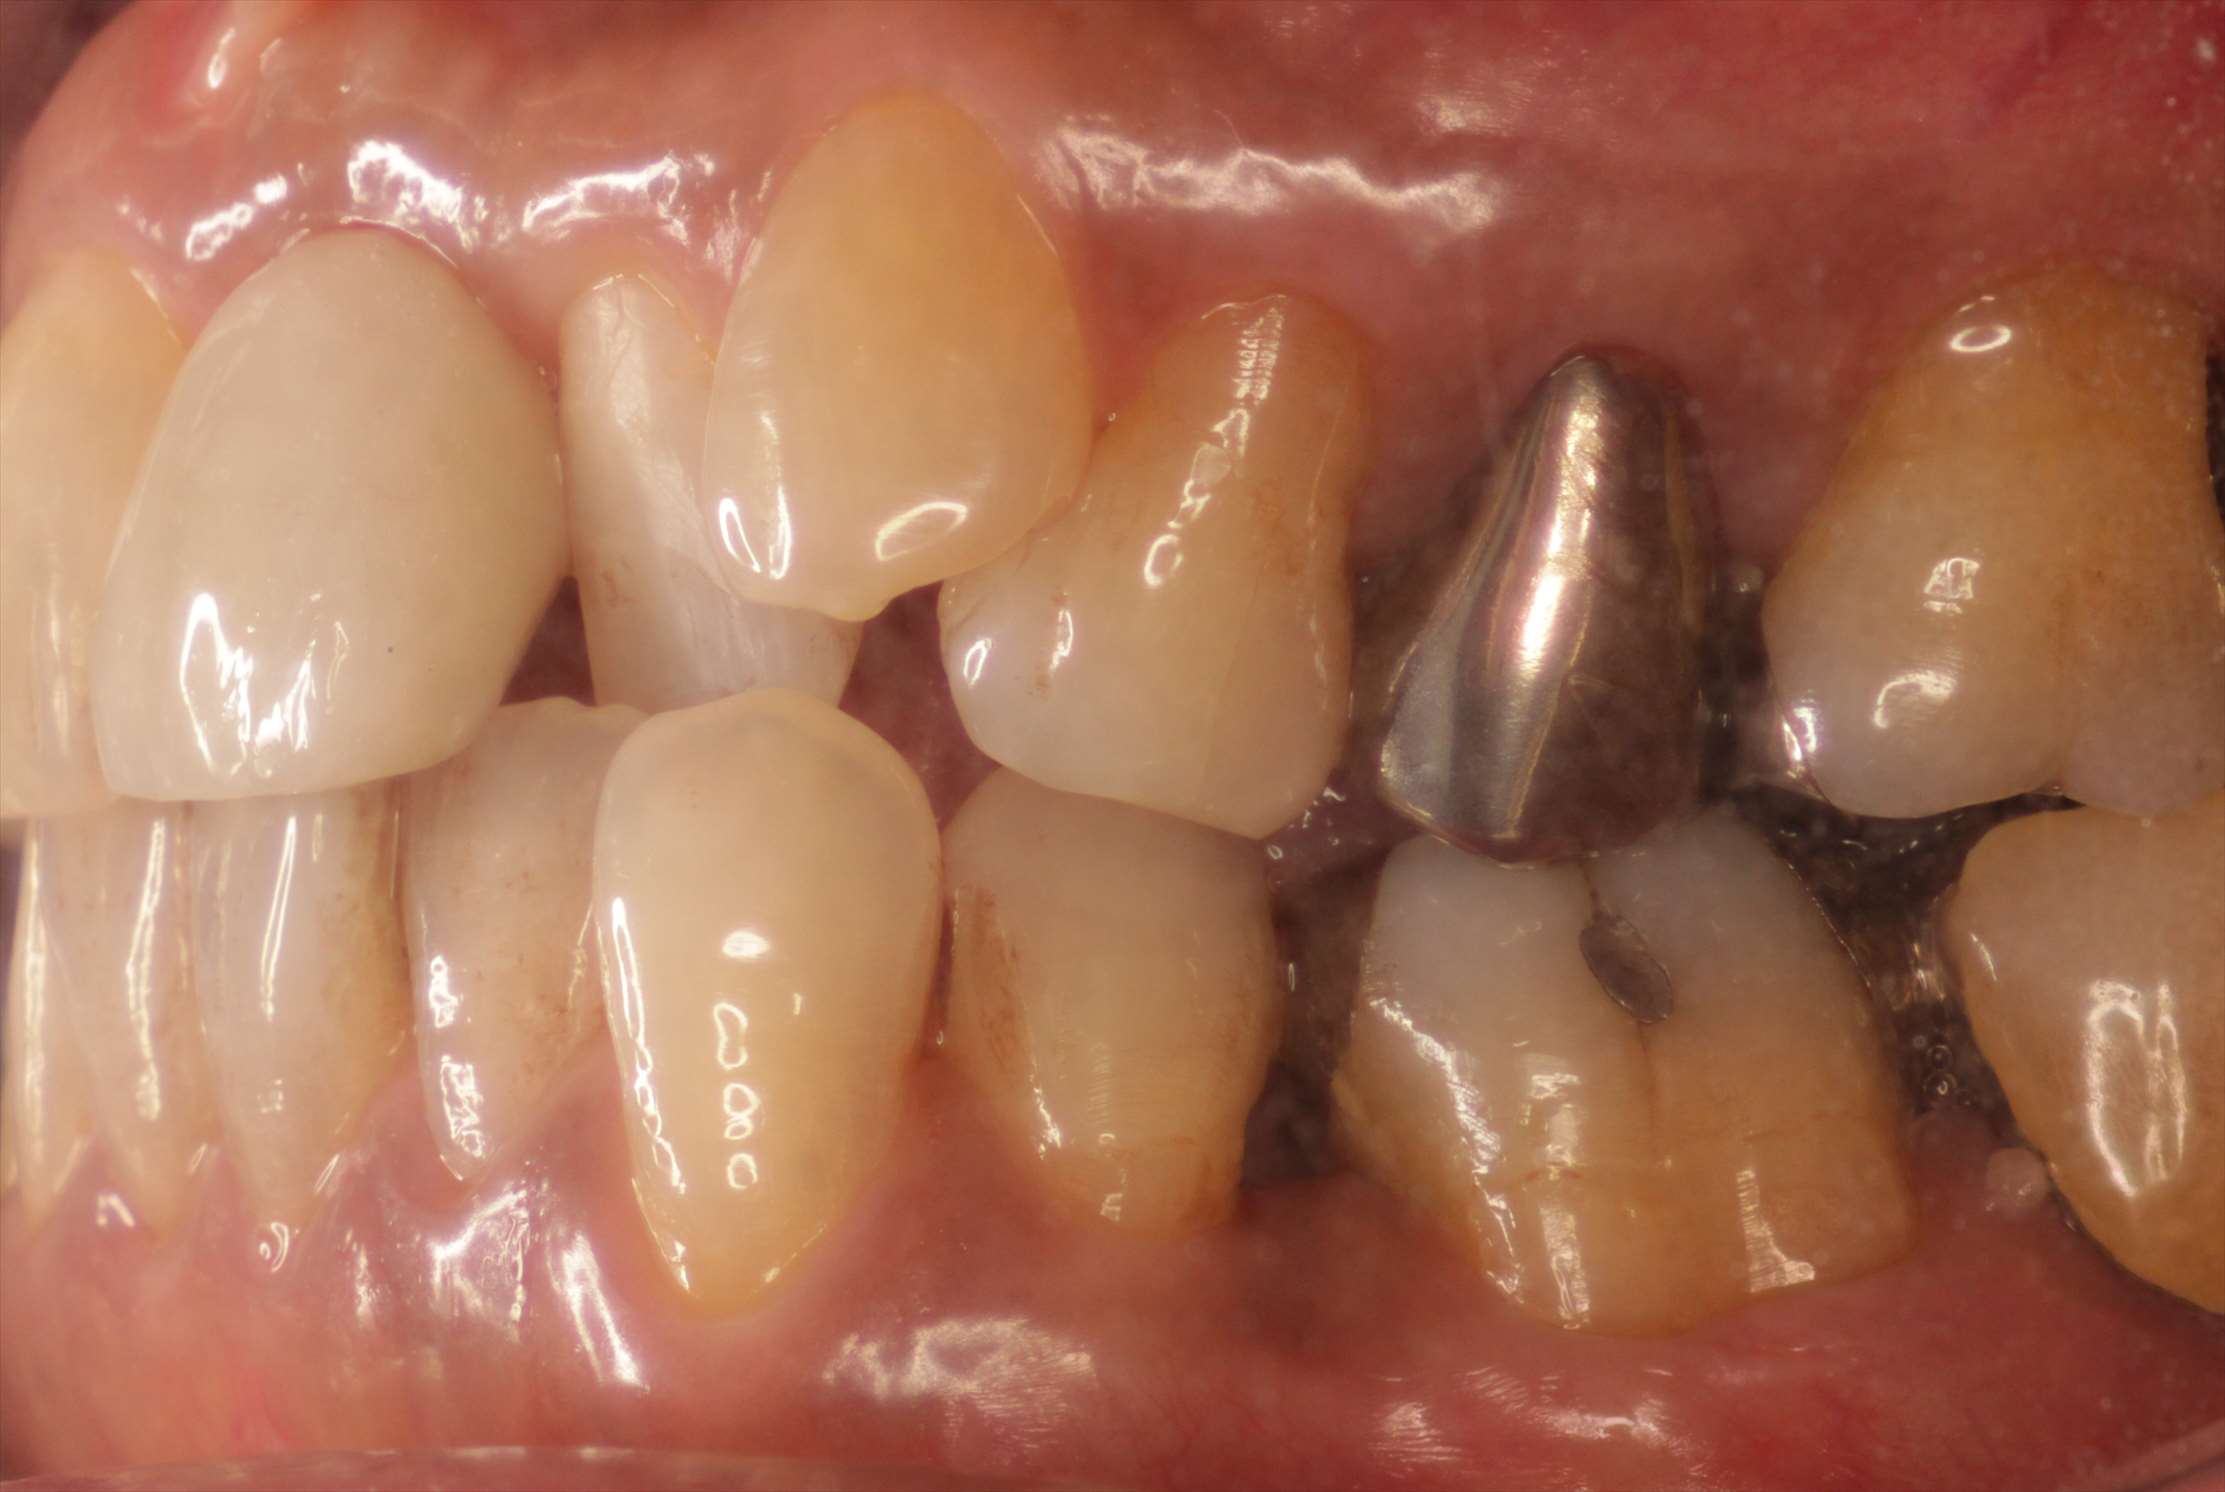

- 治療前

抜歯した左上1番の歯です。